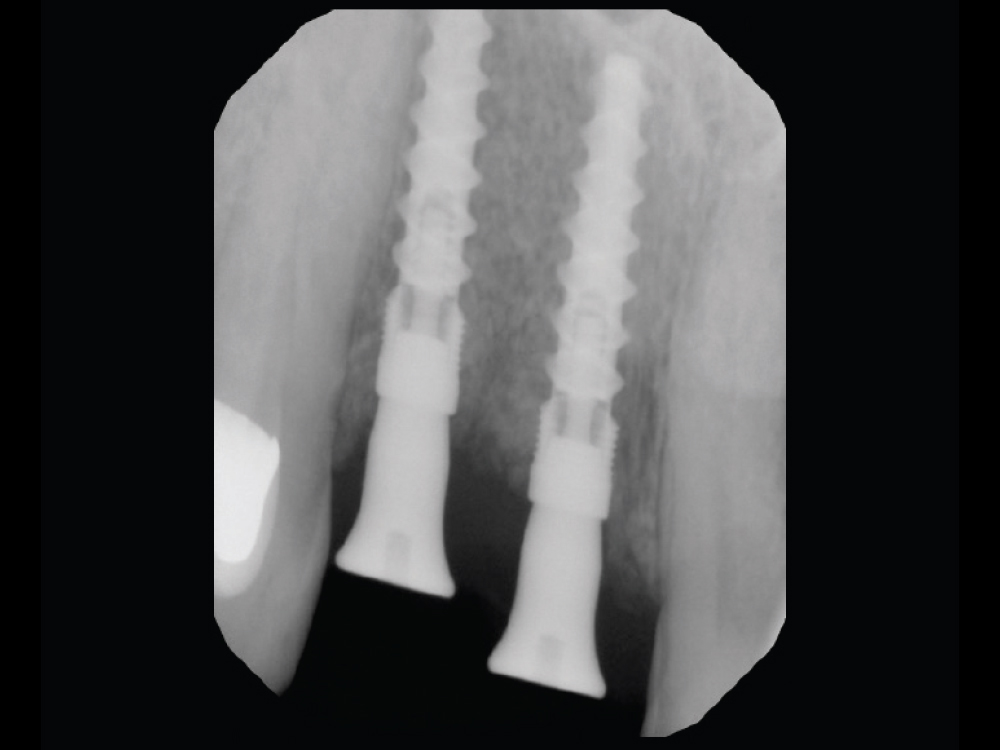

Extraction Site by Fenestration Case Pt2

Extraction Site by Fenestration Case Pt3

Extraction Site by Fenestration Cast Pt4

Extraction Site by Fenestration Cast Pt5

In this case example, an implant was immediately placed into an extraction site compromised by a fenestration. By utilizing the appropriate diagnostic, surgical and bone grafting techniques, a predictable restoration was delivered for the patient, and abundant bone volume was evident around the Hahn Tapered Implant.